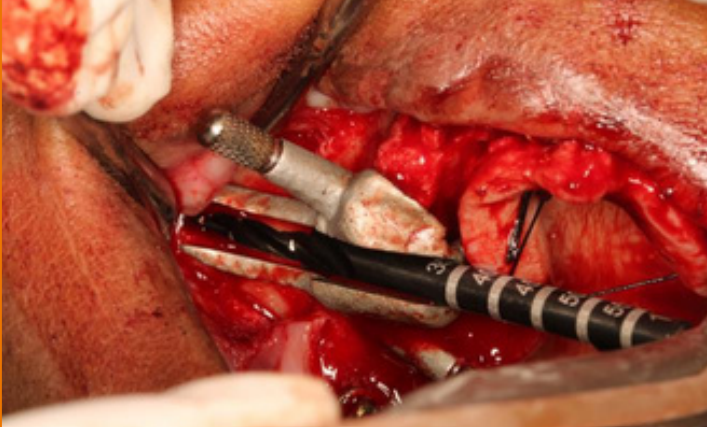

ZYGOMA CASES

ZYGOMA CASES